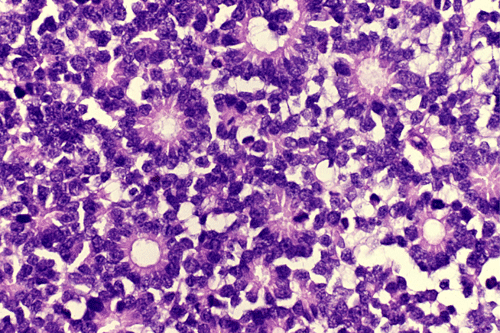

On the whole mount of the globe, there is an exophytic neoplasm that occupies about one-third the volume of the vitreous. The surface of the retina is free of tumor deposition (Panel A). The retina is detached by the mass. There are some pink, necrotic material at the core of the tumor (Panel B). On medium and high-magnification, the tumor is composed of densely packed small cells with hyperchromatic nuclei  without prominent nucleoli. A large number of the cells arrange in rossettes with a well-defined luminal border (Flexner-Wintersteiner rossettes) (Panel C and D). The tumor is confined within the globe and the optic nerve is free from invasion.

Most often, tumor cells arrange in Flexner-Wintersteiner rosettes typified by tall cuboidal cells formaing a small, circumstribed lumen with well defined limiting membrane on the luminal side. The tumor nuclei are found at the basal end of the cuboidal cells while the apical end contains the cytoplasm. Small projections are protruding from the luminal surface into the lumen and these projections represent residual features of photoreceptor cells. Homer-Wright rosettes can also be found but are less common. In between the rosettes are solid sheets of poorly differentiated tumor cells.